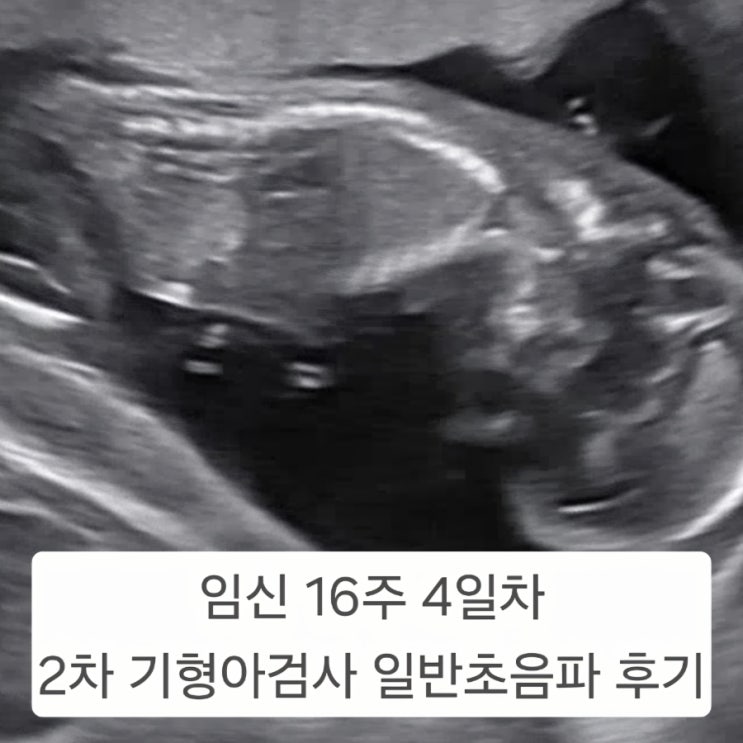

안양 봄빛병원 임신 16주 4일차 2차 기형아검사 일반초음파 동안구보건소 쿠폰 할인

안녕하세요. MZ커플입니다. 벌써 16주차가 되어 안양 봄빛병원에서 2차 기형아검사를 하고 왔어요. 안양 ...